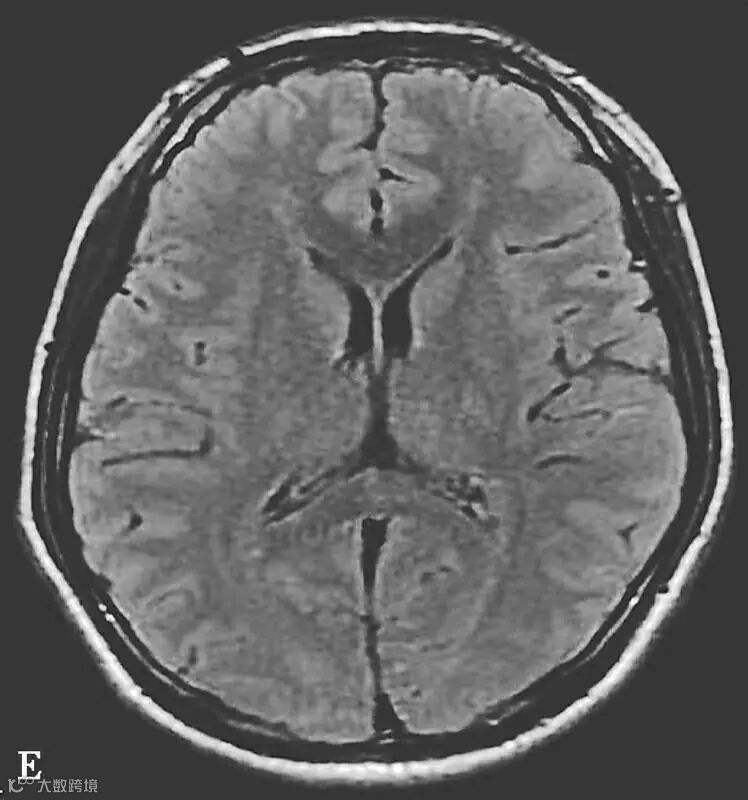

图6-11-2 弥漫性轴索损伤

男,36岁,外伤后2天。A~J(A、B.T2WI,C、D.T1WI,E、F.T2WI-FLAIR,G、H.DWI,I、J.ADC图):双侧额叶、半卵圆中心及胼胝体压部可见多发斑点状等T1稍长T2信号,边缘不清,FLAIR及DWI呈高信号,ADC图病灶信号减低 。